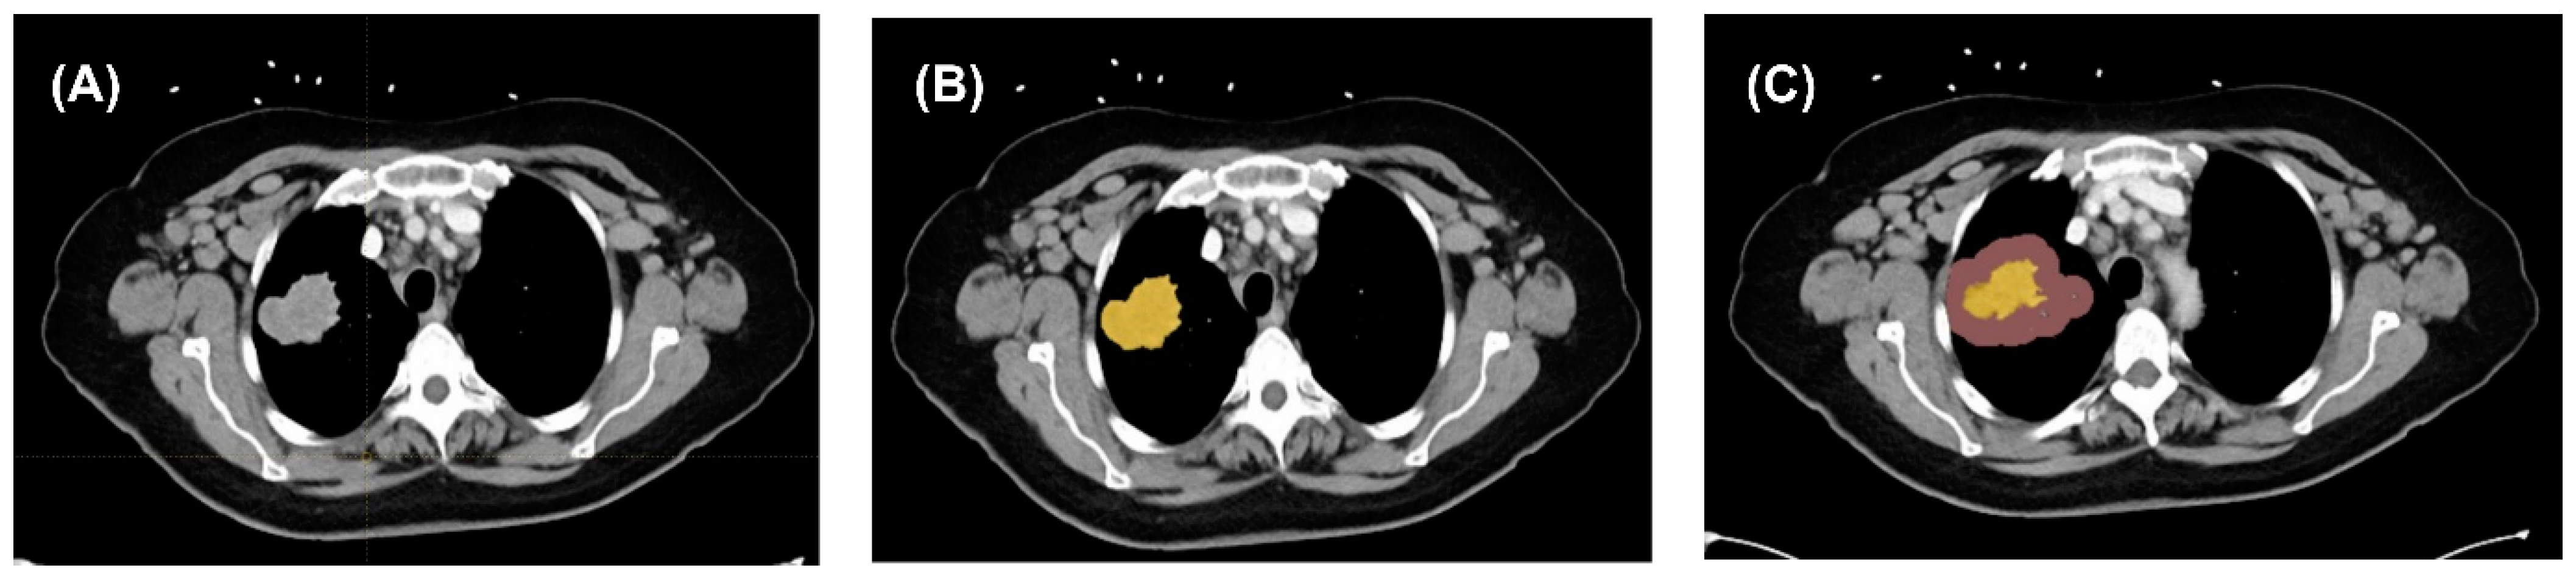

3.2. Image Segmentation and Feature Extraction